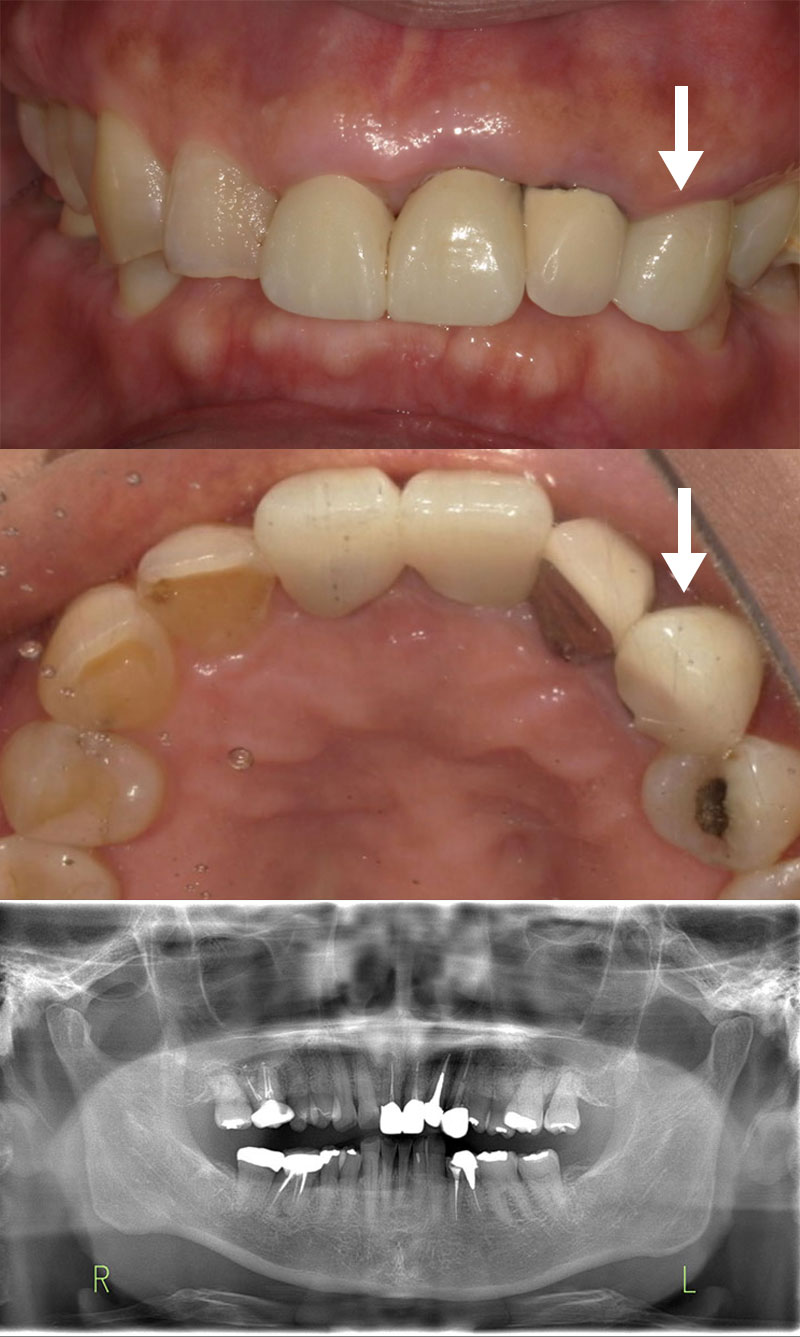

前歯のインプラント

前歯の痛みで来院された患者さま。

診査の結果、左上の犬歯が歯根破折しており保存は困難と判断し、抜歯後にインプラント治療を選択されました。

また治療にあたっては、

・歯周病で下がっていた歯ぐきの再建

・金属の目立つ被せ物をセラミックへやり替え

も治療しました。

前歯部の歯周外科は傷跡や歯ぐきの後退を最小限にする繊細な治療が必要ですが、経験豊富な歯科技工士さんと連携し、既存のセラミックとの色調再現もばっちりです。

インプラントのネジ穴(アクセスホール)も見えない位置に設計して、見た目の自然さとしっかり噛める機能性を両立しています。

治療後は「見た目も噛み心地も大満足!」と嬉しいお言葉をいただきました。

| 患者様 | 50代女性 |

|---|---|

| 主訴 | 前歯が痛い |

| 治療方法 | インプラント ジルコニアセラミック |

| 治療費 | ジルコニアセラミック費用:132,000円(税込) インプラント本体:165,000円(税込) 上部構造:198,000円(税込) ジルコニアセラミック ジルコニアアバットメント 手術検査費:12万円(税込) 骨造成:77,000円(税込) インプラント費用総額:572,000円(税込) |

| 治療期間 | 半年(約10回通院) |